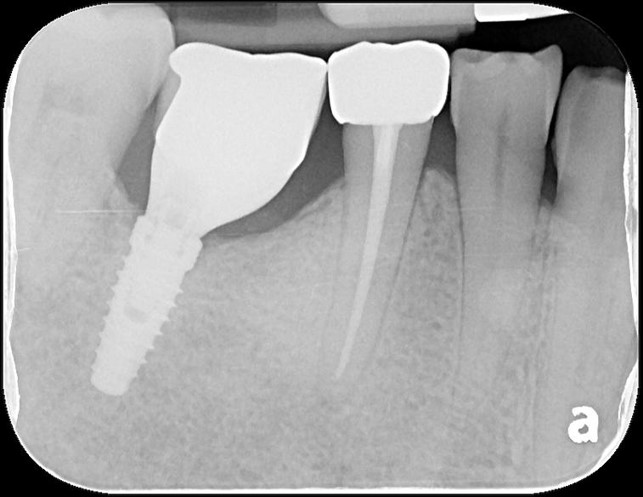

顯微根管治療

治療後根尖照